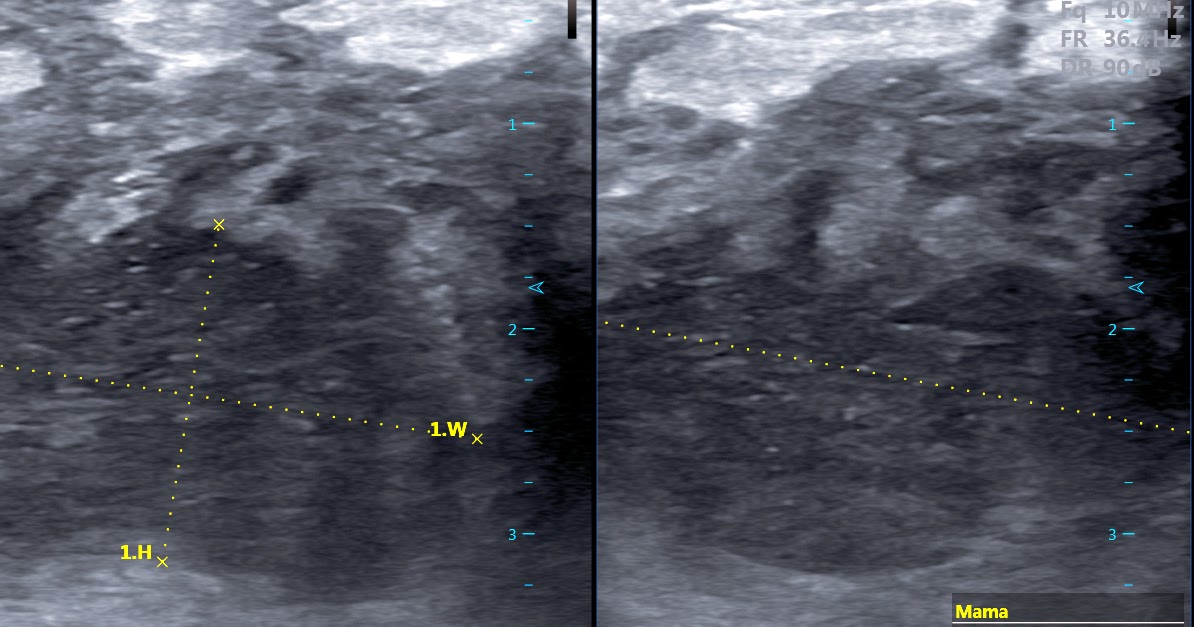

mastite com abscesso profundo